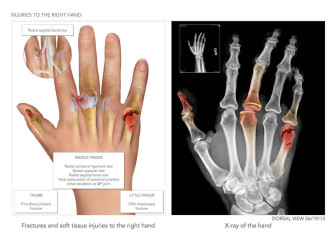

Dislocation of Wrist and Hand with Open Fractures

Available in high resolution JPEG or PDF formats, 8x10 print, or laminated foam core exhibit board (24x46, 30x40 or 36x48).